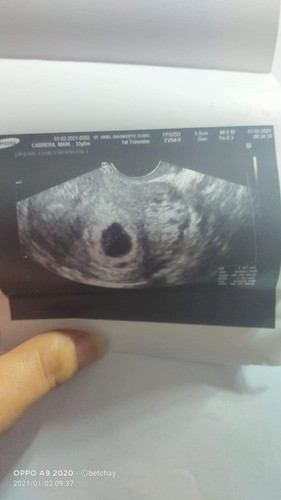

Hi i have my 1st transvi..

it's 5 weeks 6 days with gastational sack but no yolk sack.. do i need get worried about it